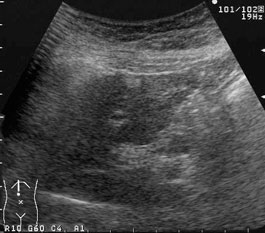

血管腫に似た1cm程度の高エコー腫瘤像である。このような腫瘤を慢性肝炎の患者に見たら、まず肝細胞癌を疑う。  |